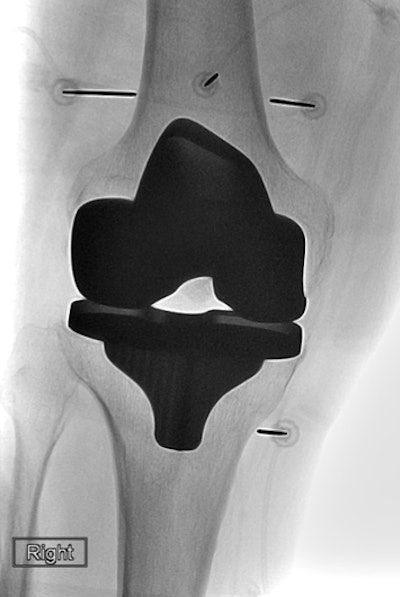

Although a growing number of patients with severe arthritis are receiving total knee arthroplasty, approximately 15% to 30% of these patients continue to experience knee pain and stiffness after the knee replacement, according to the researchers.

After demonstrating in previous research that the method can lead to lasting pain relief in people with knee, shoulder, and hip arthritis, the researchers applied cooled RF ablation in this study to 21 patients who were experiencing chronic pain after total knee replacement. All of these patients had no underlying hardware complications and had failed conservative care.